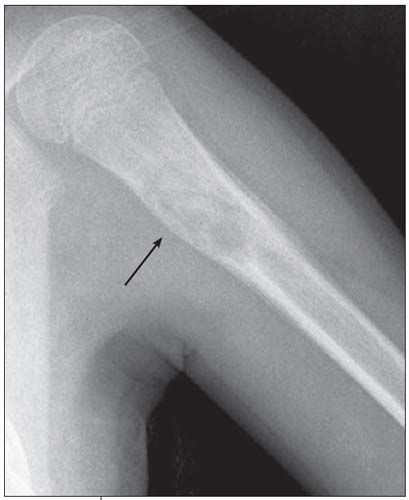

Anteroposterior and lateral views of the patient's left humerus were ordered.

The radiographs show a centrally placed lytic lesion with lobulated contours and a well-defined transition zone in the proximal shaft of the humerus. An oblique pathological fracture runs through the cyst No other lesions are visible. A thick periosteal reaction on the medial aspect of the lytic lesion is also present; the periosteal reaction is atypical in this case; however, the radiographs were obtained 10 days after the fall.

This is a unicameral, or simple, bone cyst. Many of the lesions in the differential diagnosis, including aneurysmal bone cyst, osteomyelitis, malignant lytic lesion (such as eosinophilic granuloma or bone metastasis), can be excluded on the basis of location. The location of simple bone cysts is usually the humeral head, ball of the foot, proximal femur, or proximal humerus or calcaneus.

A simple bone cyst may be an incidental finding. However, like this child, most patients present with a pathological fracture. The pathognomonic sign after a fracture is a fallen fragment in the most dependent portion of the cyst. Occasionally, a periosteal reaction can be seen. A simple bone cyst is a fluid-filled cavity lined with fibrous tissue. It is thought to result from venous outflow obstruction, which leads to an increased intraosseous pressure and a consequent stimulation of

osteoclastic activity. This benign lesion usually devel-ops within the first 2 decades of life. The cyst causes bone instability and sometimes may be associated with pathological fractures after relatively minor trauma.